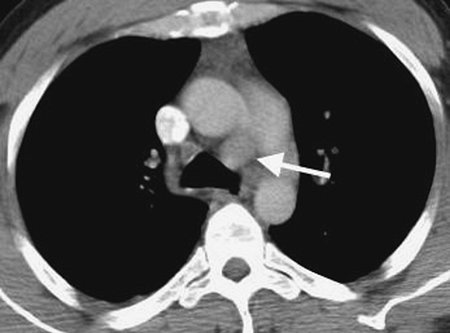

FIGURE 6-3. Parathyroid adenoma. CT shows a nonspecific enhancing mass (arrow) in the aortopulmonary window. Although commonly an anterior mediastinal mass, parathyroid adenomas can occur in any mediastinal compartment.